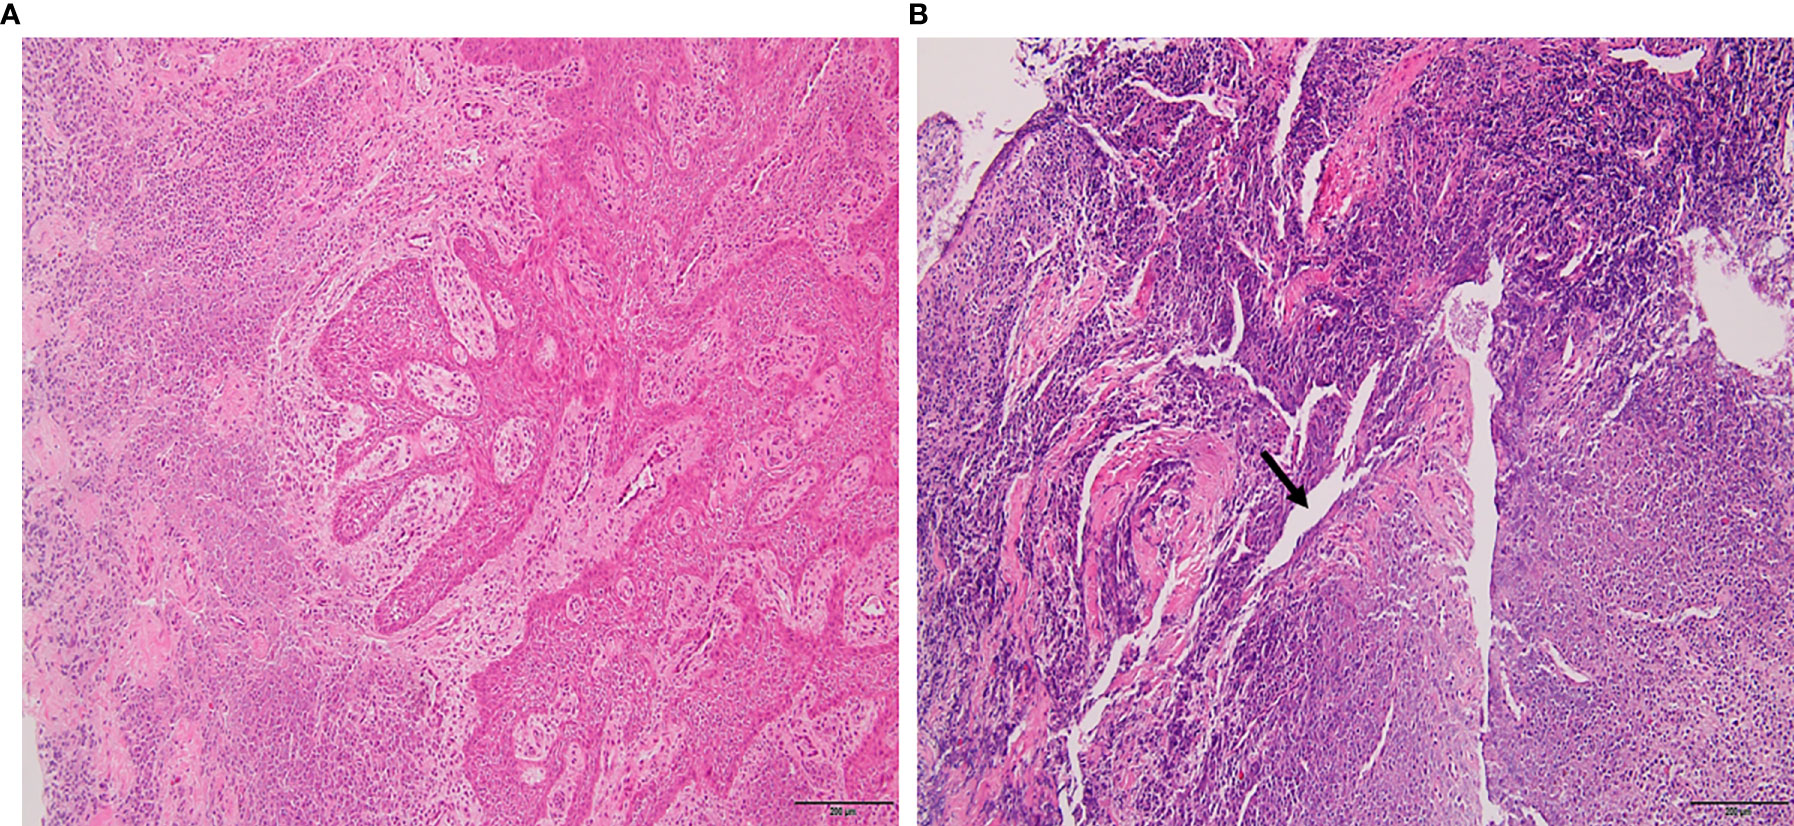

Phlegmon is an area of inflammation in the tissues while an abscess is a little bag of pus that’s more contained The way they’re treated is a different too This article will discuss a. Phlegmon is a medical term describing an inflammation of soft tissue that spreads under the skin or inside the body

It’s usually caused by an infection and produces pus Phlegmon is an area of soft tissue or fluid density effacing or displacing usual fat or other connective tissue and shows variable enhancement However, an abscess typically has a. A phlegmon is a localized area of acute inflammation of the soft tissues

Instead the infection spreads along tissue planes and between muscle fibers. Phlegmon is a serious skin infection that affects the soft tissues, leading to inflammation and a collection of pus It is often caused by bacteria entering the skin through a. This article explores the causes, symptoms, diagnosis, and treatment of phlegmon, including its classifications based on clinical course, severity, location, cause, pathogenesis,.